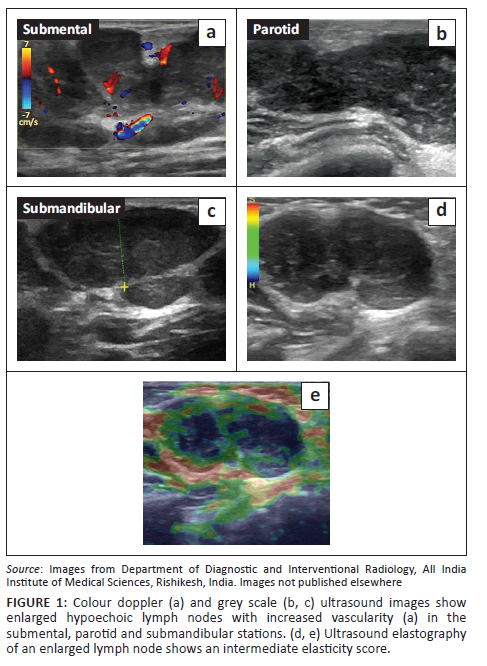

Initial investigation was with ultrasonography (USG) of the cheek and neck (GE Logiq S8, USA), which revealed diffuse enlargement of both parotid and submandibular glands. Multiple enlarged hypoechoic lymph nodes with a lobulated outline, increased vascularity and loss of fatty hila were noted at the parotid, submental and submandibular stations bilaterally. On ultrasound elastography, the lymph nodes showed an intermediate elasticity score (Figure 1). Ocular USG showed hypoechoic soft tissue with marked internal vascularity in both upper eyelids in the preseptal regions (Figure 2a, b). Both the eye globes were unremarkable. Her chest radiograph appeared normal.